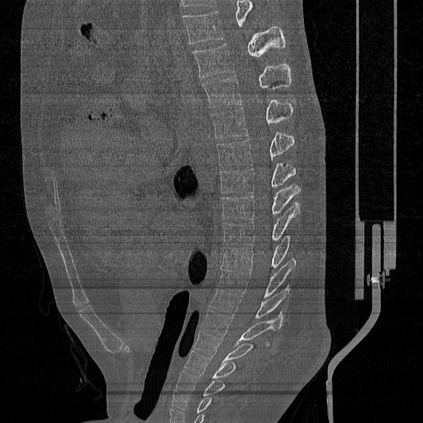

CT reconstruction provides radiologists with images for diagnosis and treatment, yet current deep learning methods are typically limited to specific anatomies and datasets, hindering generalization ability to unseen anatomies and lesions. To address this, we introduce the Multi-Organ medical image REconstruction (MORE) dataset, comprising CT scans across 9 diverse anatomies with 15 lesion types. This dataset serves two key purposes: (1) enabling robust training of deep learning models on extensive, heterogeneous data, and (2) facilitating rigorous evaluation of model generalization for CT reconstruction. We further establish a strong baseline solution that outperforms prior approaches under these challenging conditions. Our results demonstrate that: (1) a comprehensive dataset helps improve the generalization capability of models, and (2) optimization-based methods offer enhanced robustness for unseen anatomies. The MORE dataset is freely accessible under CC-BY-NC 4.0 at our project page https://more-med.github.io/